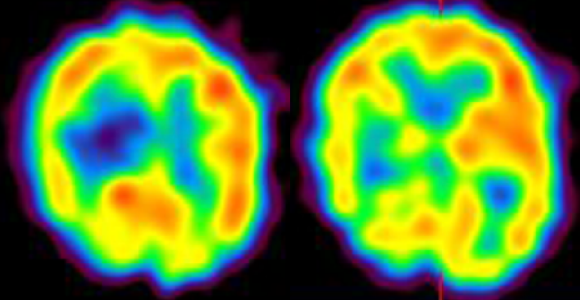

脳動脈瘤、もやもや病などの閉塞性脳血管障害、 脳血管奇形における病態研究を行っています。 特に、若年者の脳卒中の原因として近年増加傾向にある指定難病もやもや病に関しましては 長年の診療経験を踏まえて、遺伝子研究やバイパス周術期病態の解明を中心に先進的研究を推進しています。 もやもや病に対するバイパス手術はガイドラインでも標準治療として推奨されていますが、 術後急性期に局所過灌流(一時的な流れすぎ)や特異な脳虚血病態(watershed shift現象)など、 もやもや病に特徴的な病態を呈することを見出しました。 さらなる治療成績向上を目指して術後急性期の病態解明を脳循環画像やMRIを駆使して推進しています。 また、くも膜下出血の原因として重要な脳動脈瘤に関して高感度MRIを用いた動脈瘤壁イメージング(vessel wall imaging)を 駆使した動脈瘤増大・破裂に関する病態研究を進めています。